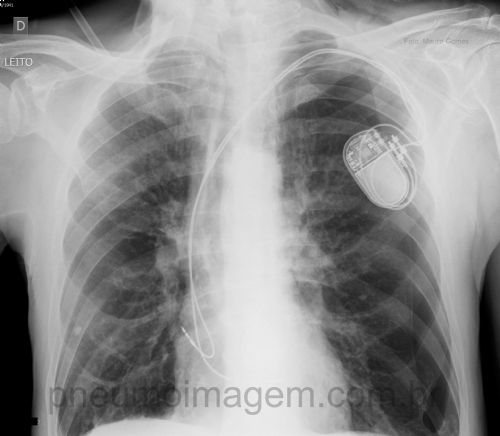

CASO CLÍNICO #11Paciente do sexo masculino, 70 anos de idade, portador de DPOC classe C, apresentou quadro de hipersensibilidade do seio carotídeo e necessitou ser submetido à colocação de marca-passo cardíaco definitivo. Após o procedimento desenvolveu quadro de insuficiência respiratória aguda e necessitou ser transferido à UTI. Faça sua hipótese diagnóstica e deixe os seus comentários abaixo.

Male patient, 70 years-old, COPD C, presented with carotid sinus hypersensitivity and needed to be submitted to the placement of permanent cardiac pacemaker. After the procedure he developed acute respiratory failure and needed to be transferred to the ICU. Leave your comments below.

Diagnóstico é Pneumotórax a esquerda cujo tratamento é drenagem torácica fechada!!!!

Pneumotórax à E